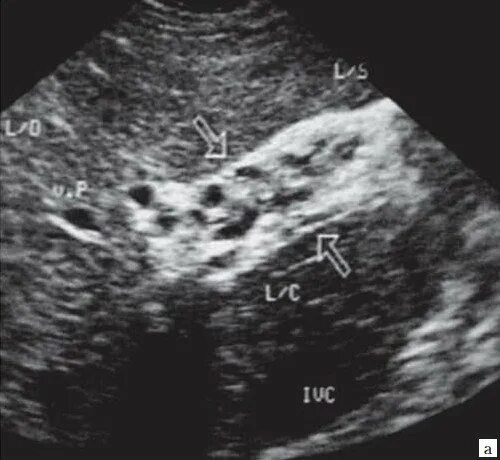

Уплотнение внутрипеченочных протоков